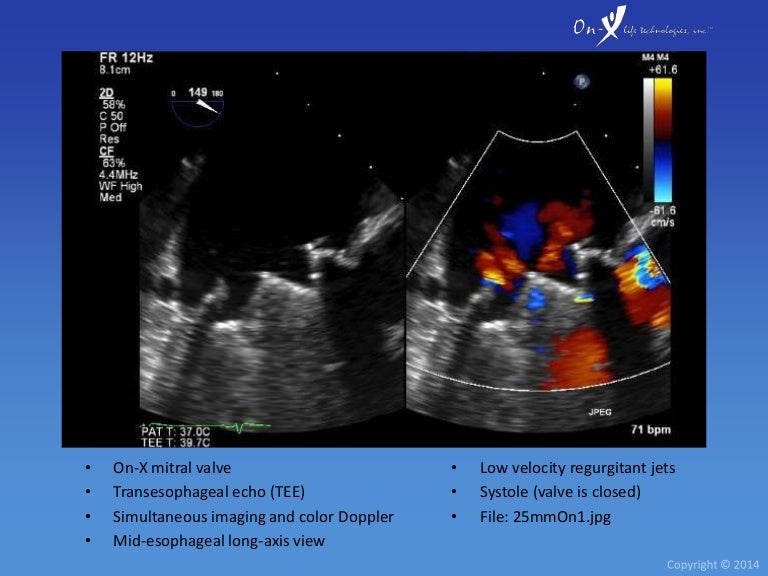

From www.slideshare.net

OnX Heart Valve Echocardiography How Long Does An On-X Valve Last The only aortic mechanical valve with fda, health canada, and ce. it is recommended that anticoagulation therapy is stopped 2 to 4 days prior to the procedure so that the inr falls to <1.5, and. Operative mortality occurred in 26. multivariable analysis showed that mortality increased with total length of stay, age, smoking history, severe. this study. How Long Does An On-X Valve Last.